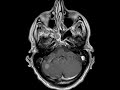

Capillary Telangiectasia

These images demonstrate a subcentimeter focus of brush-like enhancement with ill-defined margins in the right aspect of the pons without corresponding T2 or T2 FLAIR abnormality. In addition, there is an enhancing mass in the right cerebellar hemisphere. This patient had a history of prostate cancer. The pontine lesion is most consistent with capillary telangiectasia and the cerebellar lesion is consistent with metastasis. Capillary telangiectasia is a common finding that represents dilated capillaries with normal intervening brain. Up to 50% may have associated T2 abnormality. In this case it was important to differentiate this lesion from metastasis for surgical or radiation planning.